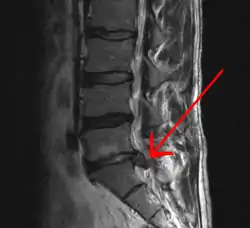

Imaging is indicated when there are red flags, ongoing neurological symptoms that do not resolve, or ongoing or worsening pain.[5] In particular, early use of imaging (either MRI or CT) is recommended for suspected cancer, infection, or cauda equina syndrome.[5] MRI is slightly better than CT for identifying disc disease; the two technologies are equally useful for diagnosing spinal stenosis.[5] Only a few physical diagnostic tests are helpful.[5] The straight leg raise test is almost always positive in those with disc herniation,[5] and lumbar provocative discography may be useful to identify a specific disc causing pain in those with chronic high levels of low back pain.[44] Therapeutic procedures such as nerve blocks can also be used to determine a specific source of pain.[5] Some evidence supports the use of facet joint injections, transforminal epidural injections and sacroiliac injections as diagnostic tests.[5] Most other physical tests, such as evaluating for scoliosis, muscle weakness or wasting, and impaired reflexes, are of little use.[5]

Complaints of low back pain are one of the most common reasons people visit doctors.[45][46] For pain that has lasted only a few weeks, the pain is likely to subside on its own.[47] Thus, if a person's medical history and physical examination do not suggest a specific disease as the cause, medical societies advise against imaging tests such as X-rays, CT scans, and MRIs.[46] Individuals may want such tests but, unless red flags are present,[48][49] they are unnecessary health care.[45][47] Routine imaging increases costs, is associated with higher rates of surgery with no overall benefit,[50][51] and the radiation used may be harmful to one's health.[50] Fewer than 1% of imaging tests identify the cause of the problem.[45] Imaging may also detect harmless abnormalities, encouraging people to request further unnecessary testing or to worry.[45] Even so, MRI scans of the lumbar region increased by more than 300% among United States Medicare beneficiaries from 1994 to 2006.[10]